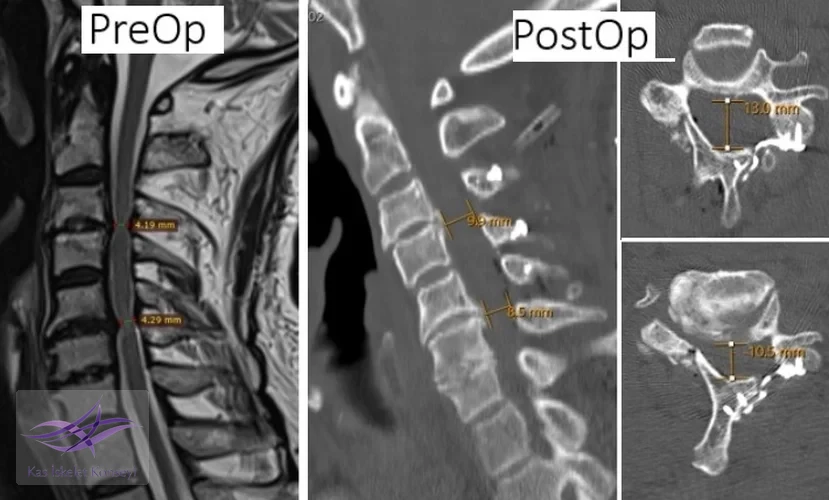

İncelemeler: Servikal MRG'de dar kanal saptandı, kanal ön-arka çapı 5 mm'nin altına inmişti.

Klinik Seyir: Hastaya cerrahi dekompresyon kararı verildi. C3-C6 seviyelerinde servikal laminoplasti yapıldı. Postop BT incelemelerinde kanal çapının arttığı görüldü. Hastada cerrahiye ait bir komplikasyon olmadı ve klinik durum belirgin düzeldi.

Resim 1. Preop MRG incelemelerinde servikal dar kanal ve omurilikte myelopatik değişiklikler görülmekte.

Resim 2. Preop ve postop incelemelerde kanal çapındaki artış görülmekte.